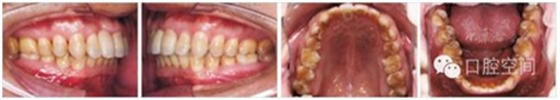

30歲男性患者,由于下前牙經(jīng)常咬傷上牙腭側(cè)牙齦,要求矯正調(diào)整咬合關(guān)系。上頜粘接直絲弓矯治器2個(gè)月后,下頜開(kāi)始固定矯治,排齊牙列。4個(gè)月后下頜更換至0.018英寸鎳鈦絲,在下頜中切牙之間前庭溝處,局麻下切開(kāi)黏膜,正中聯(lián)合部位植入一顆微螺釘(1.6 mm×9 mm,慈北醫(yī)療器械有限公司)。以直徑0.30 mm結(jié)扎絲連接微螺釘頭部,并穿出黏膜形成牽引鉤形狀。一周后開(kāi)始加力,以微螺釘種植體支抗行閉合式牽引壓低下頜切牙。10個(gè)月后下切牙壓低良好,前牙覆頜正常,去除支抗螺釘。固定矯治20個(gè)月后,進(jìn)入保持階段?;颊呙骖M像、X線片及頭影測(cè)量重疊圖見(jiàn)圖4,圖5,圖6,圖7,圖8,圖9,治療前后頭影測(cè)量結(jié)果見(jiàn)表2。

圖4病例1治療前面像及X線片

圖5病例1治療中像,以微螺釘支抗閉合式牽引開(kāi)始?jí)旱拖虑醒?br/>

圖6病例1治療中像,前牙覆正常

圖7病例1治療后面像及X線片

圖8病例1保持半年后像